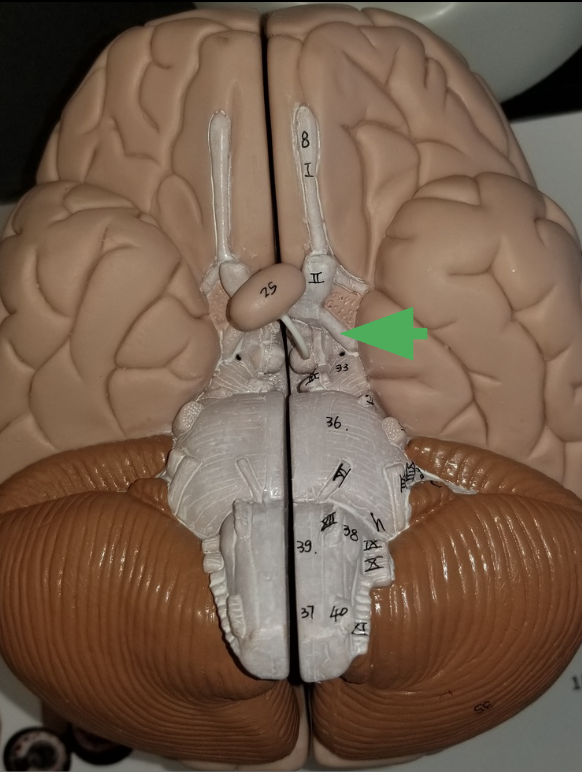

What does the arrow indicate?

Optic Track

What does the optic track do?

carry axons from optic nerves ro the thalamus